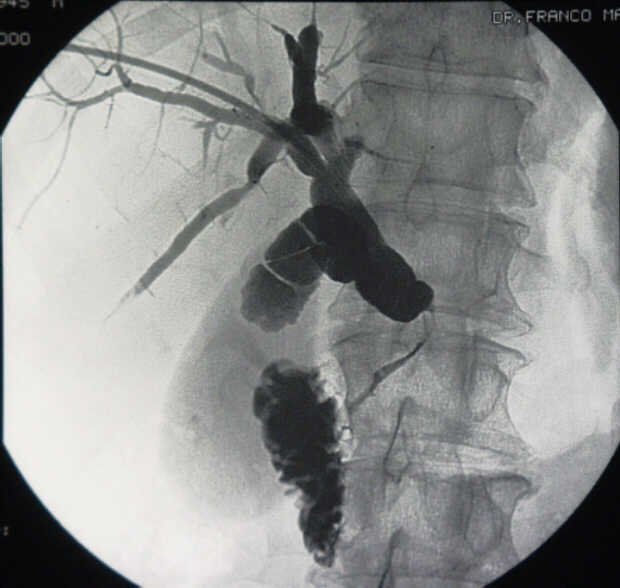

Pancreatic Head Mass: What Can Be Done?

Diagnosis: Angiography

Giuseppe Morelli Coppola, Raffaella Niola, Franco Maglione

Unità Operativa di Radiologia Vascolare ed Interventistica, Azienda Ospedaliera "A. Cardarelli". Napoli, Italy